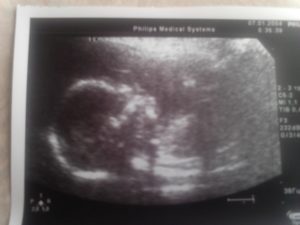

УЗИ на 19 неделе беременности поможет проконтролировать процесс внутриутробного развития.

6. Плод на 19 неделе беременности – УЗИ. Ультразвуковое исследование показывает черты лица малыша. Они видны не отчетливо, но для мамы это неповторимый момент.

Расшифровка УЗИ на 19 неделе беременности

УЗИ 19 недель беременности. При ультразвуковой диагностике наблюдается, как проходит развитие плода. Сердцебиение малыша и функционирование дыхательной системы в приоритете. Однако другие органы и процессы не остаются без внимания.